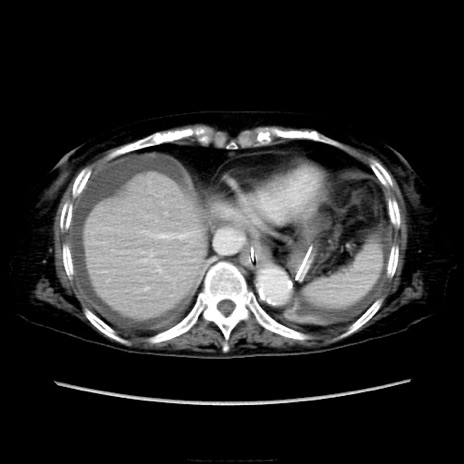

症例40(横断像)

他院CT

横断像